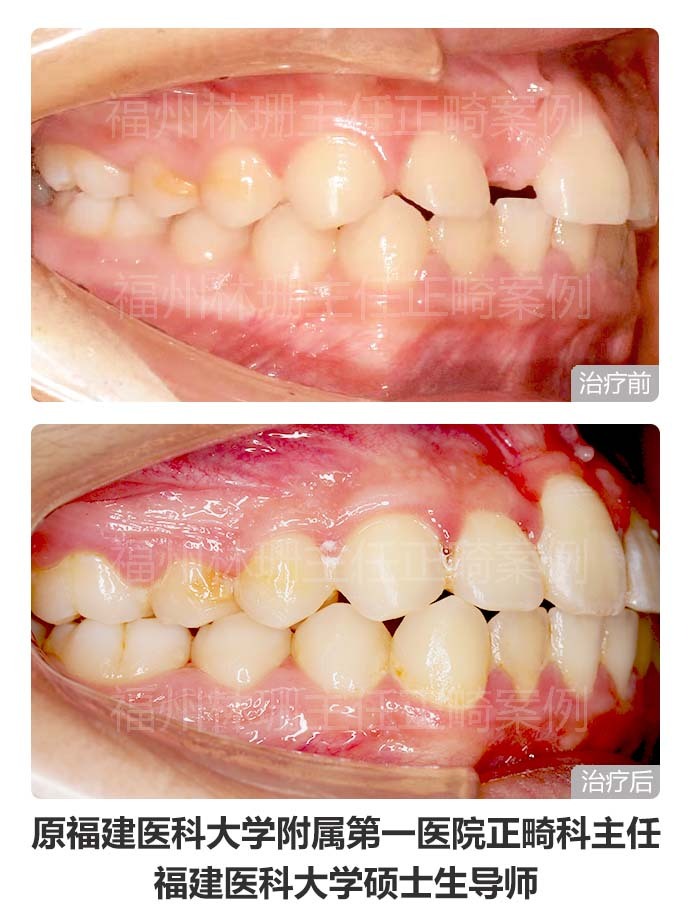

患者主诉替牙后发现上门牙未萌出,前来就诊。 检查双侧面部基本对称,侧貌直。口内检查示右上中切牙未萌出,右上侧切牙与左上中切牙存间隙。上牙列稍不齐。上中线右偏2mm,下中线正。cbct示:右上中切牙倒置阻生,合方见一多生牙。 考虑患者侧貌可,牙列拥挤度不大,且上牙列存有间隙,可通过适当扩弓拓展间隙。因此选择非拔牙矫正,利用扩弓提供的间隙牵引埋伏阻生的右上中切牙,排齐整平上下牙列,调整中线。 矫正后埋伏阻生的右上中切牙已牵引到位。上下牙列整齐,上下牙弓形态佳,上下牙弓匹配;上下前牙覆合覆盖良好,后牙咬合关系良好,上下中线正,同时维持良好侧貌。